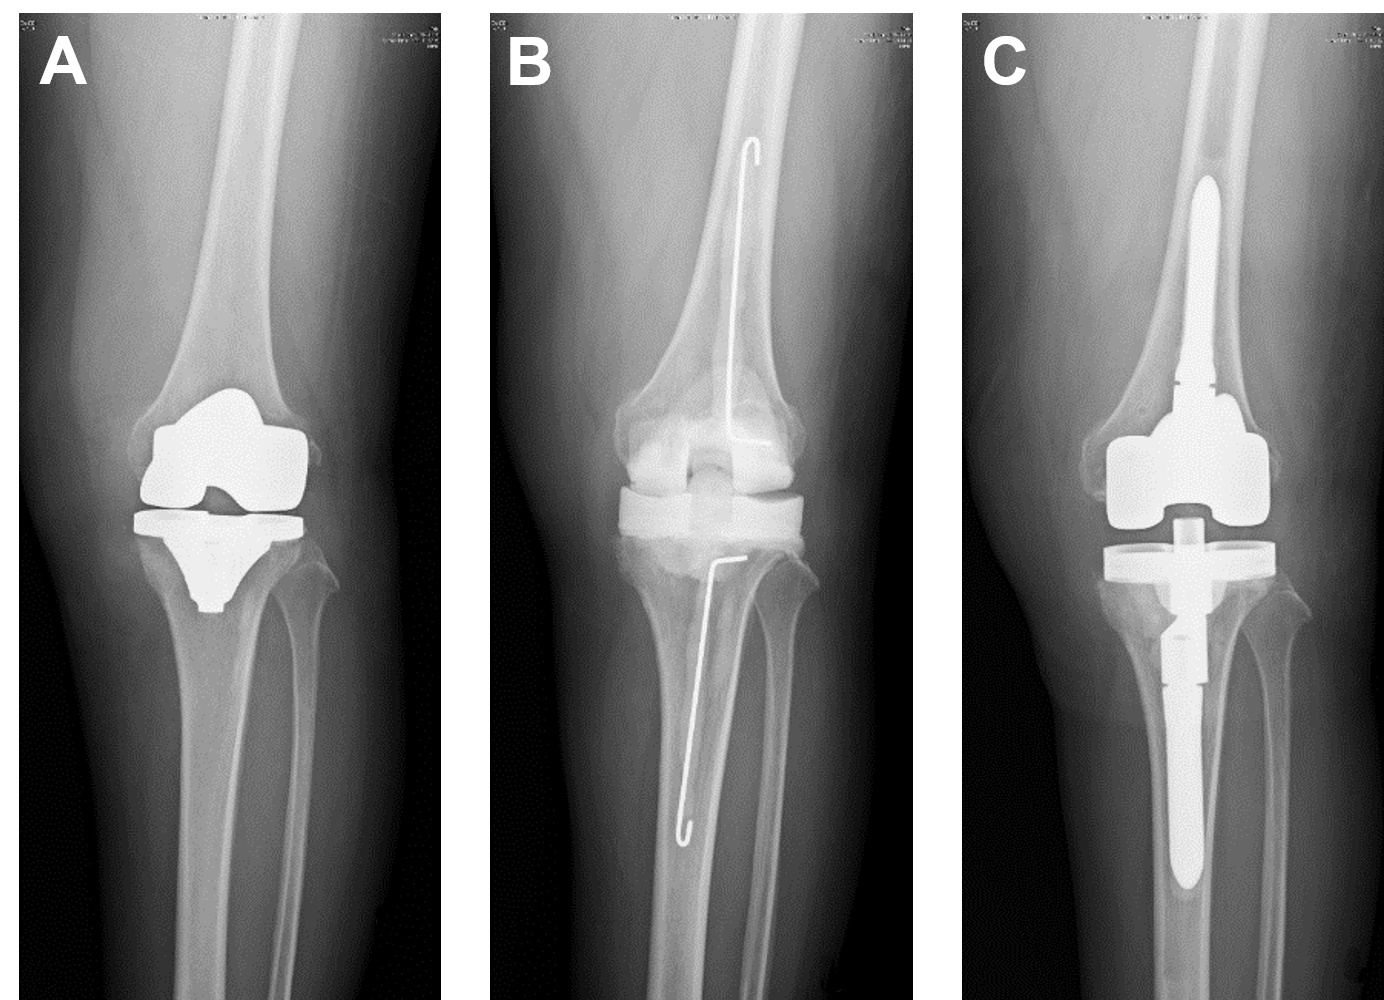

Figure 1. Representative radiographs of prosthetic joint infection (PJI). PJI diagnosis can be challenging and sometimes is based on clinical suspicion with no clinical, laboratory, or radiographic features that can confirm the diagnosis. Therefore, a point-of-care diagnostic device that can accurately diagnose PJI would be highly beneficial. In this case, (A) the image did not reveal PJI, but wound discharge indicated that the patient had developed PJI after a total knee replacement. (B) Metal prothesis was removed, soft tissues were debrided, and temporary antibiotic bone cement spacer was inserted. (C) Permanent total knee replacement was inserted after well-controlled infection.